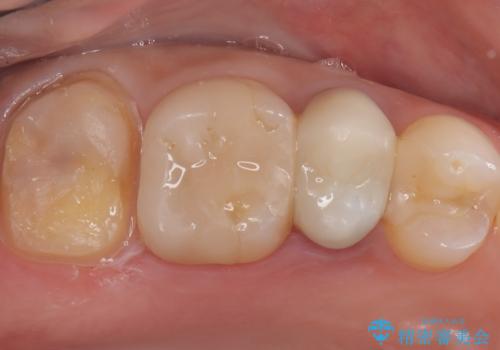

詰め物が欠けた 〈セラミッククラウン〉

- 何年も前に入れた詰め物が取れたとのことで来院されました。残っている歯の量と強度のことをお話しし、被せものでの治療となりました。

もともとの修復材料とう蝕を除去し、CR裏層の上、オールセラミッククラウンにて修復しました。